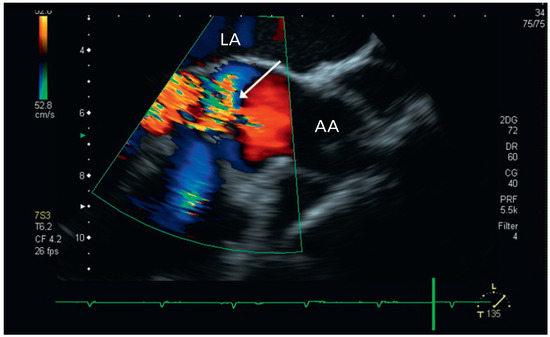

Aortic Valve Rupture Due to a Motorcycle Accident

by Daniela Vocke, Igal Moarof, Peter Matt and Pablo Anabitarte

Cardiovasc. Med. 2011, 14(6), 192; https://doi.org/10.4414/cvm.2011.01597 - 29 Jun 2011

A 62-year-old male patient was admitted as a result of a motorcycle accident [...] Full article